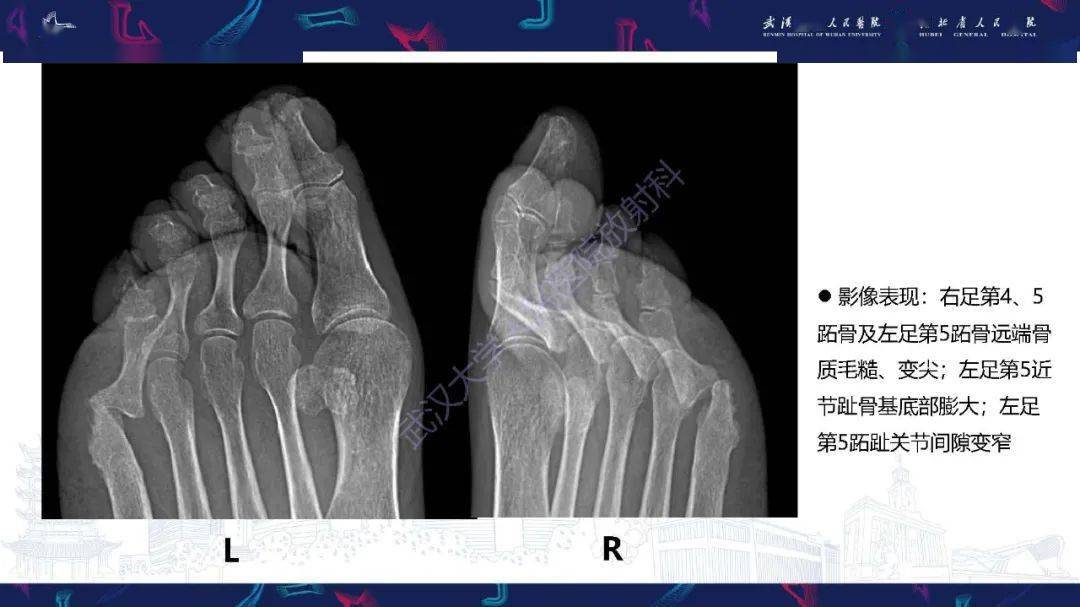

病例分享:银屑病关节炎影像表现

228psoriaticarthritis银屑病关节炎

银屑病关节炎影像诊断